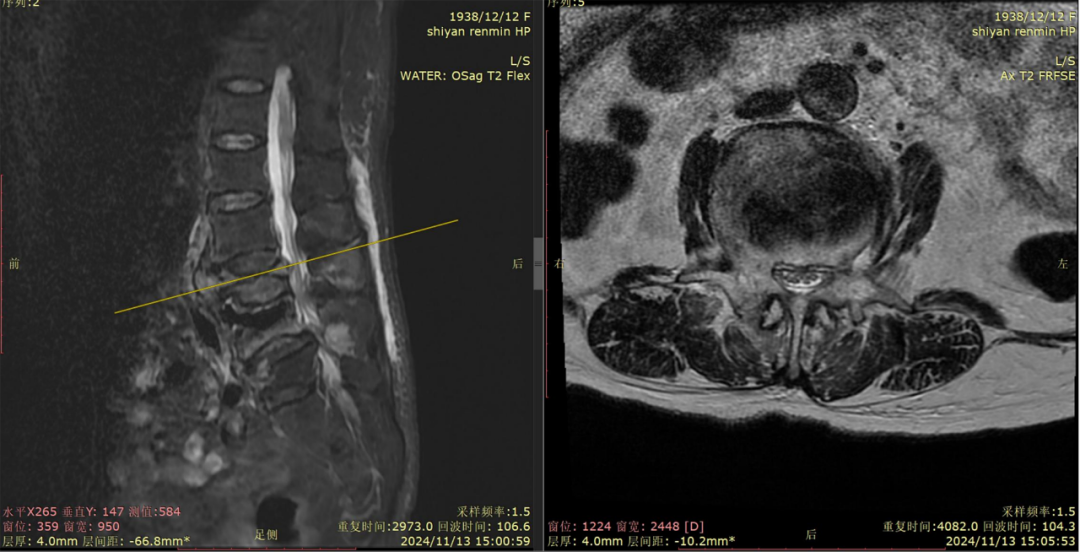

經過檢查發(fā)現(xiàn),老人嚴重骨質疏松,同時連續(xù)三個腰椎骨折,神經嚴重受壓,患者不全癱瘓,入院時屈髖、伸膝不能,雙下肢僅能勉強抬離床面5-10cm,更別說站立了。

▲張奶奶的三處腰椎骨折(標紅處為骨折內巨大空腔、標綠處為陳舊性骨折、標黃處為受壓到極限的馬尾神經)。